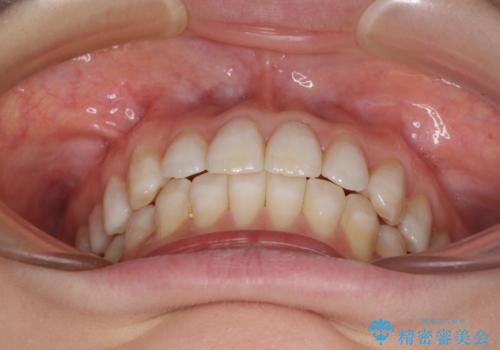

話しにくいオープンバイト インビザラインによる矯正治療

- 前歯の上下スペースによる話しにくさを気にして来院された患者様です。

インビザラインにより上下の前歯の隙間を閉じていくこととしました。

上下の奥歯を圧下させるようにすることで、前歯を接触させるように計画しました。

隙間に舌が入り込むことが話しにくさに繋がっていたため、舌の筋肉のトレーニングも並行して行い、話しにくさの改善と後戻りの抑制を図りました。